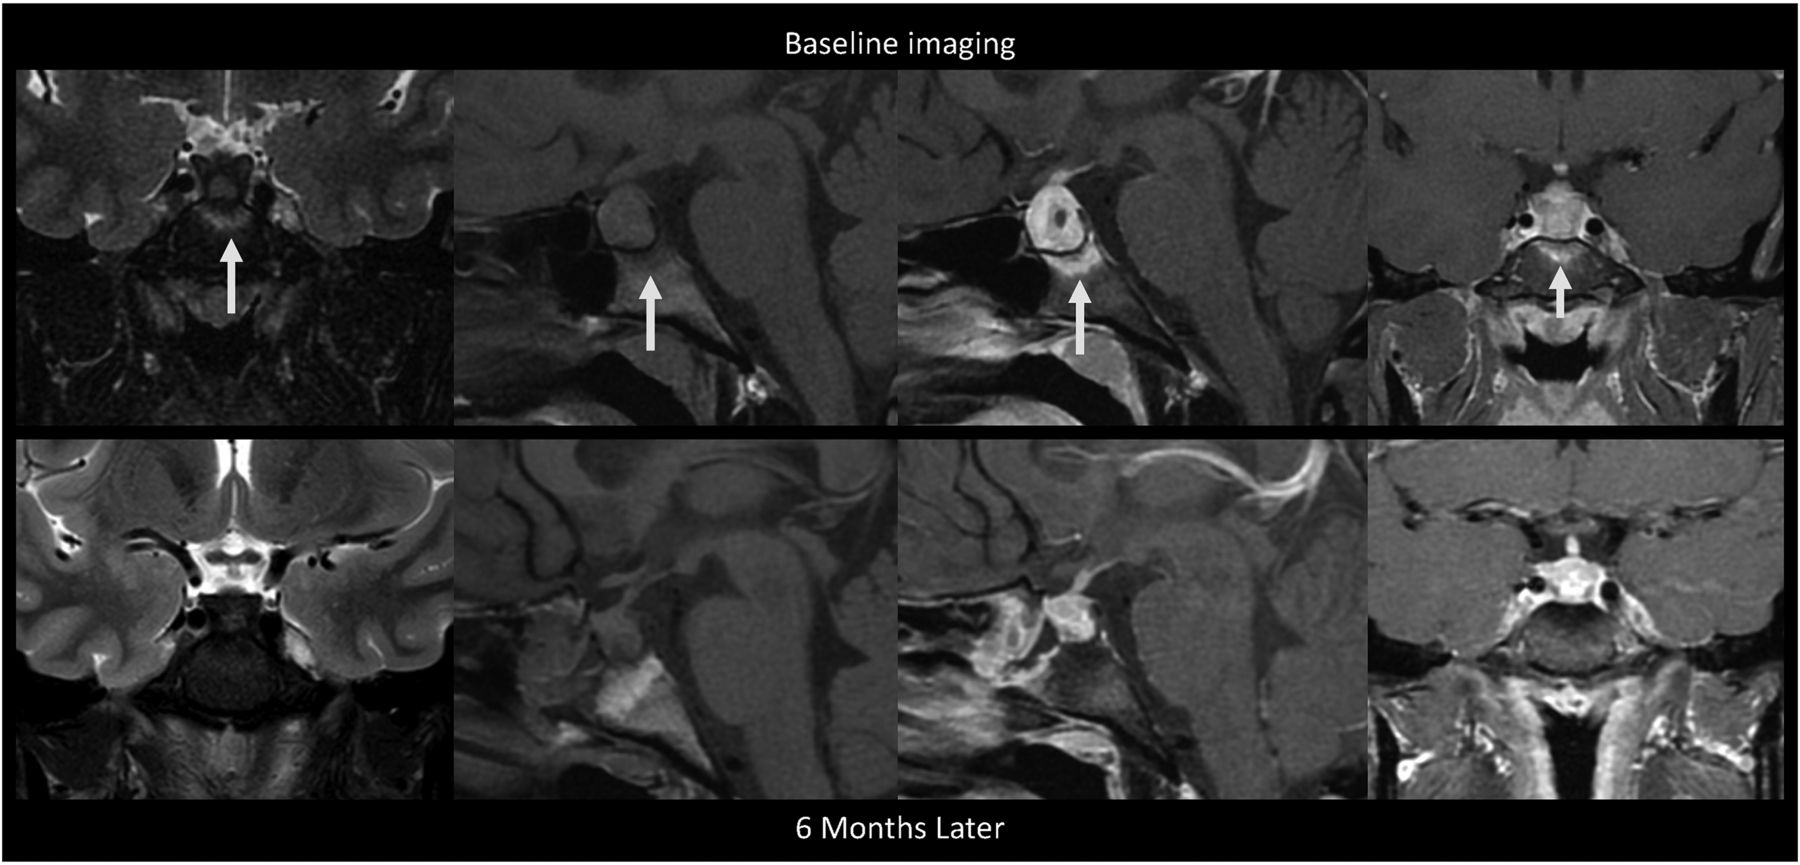

A 30-year-old woman presented with right orbital headaches, polydipsia, and polyuria (Fig 3). She was found to have hyperprolactinemia (49.5 μg/L) and a 1.7-cm sellar mass with type 3 pneumatization of the sphenoid sinus and diffuse enhancing bone marrow of the basisphenoid below the sella on MRI, thought to be a pituitary adenoma. She underwent a pituitary biopsy, findings of which were consistent with GH. Following the biopsy, she was treated with dexamethasone and desmopressin. Follow-up MRI 6 months later showed a decrease in the size of the pituitary gland and resolved bone marrow enhancement of the basisphenoid. A cervical lymph node biopsy for work-up of sarcoidosis was negative. She did not have a diagnosis of a granulomatous systemic disease, and her pituitary lesion was thought to represent primary, idiopathic GH. At follow-up 1.5 years after biopsy, the patient did not have symptoms of hypopituitarism, and her diabetes insipidus had resolved.

MR images of patient 2 with idiopathic GH and type 3 (sellar) sphenoid sinus pneumatization. This is a collage of images of a single patient at baseline before intervention (upper row) followed by postbiopsy and post-steroid treatment. Left to right, Coronal T2-weighted, precontrast sagittal T1-weighted, fat-saturated postcontrast sagittal T1-weighted, and fat-saturated postcontrast coronal T1-weighted images show diffuse infrasellar basisphenoid bone marrow–enhancing edema (arrows) on baseline that resolved 6 months later after biopsy and steroids.